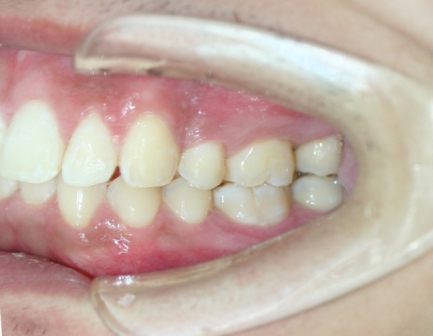

口内检查 :上下牙弓均为卵圆形 左右基本对称 上颌牙弓轻度拥挤 下颌缺失一颗下切牙

左右侧磨牙均为一类咬合关系,前牙深覆合、深覆盖。

临床 前牙深覆合,深覆盖,后牙中性关系

上下前牙唇倾

双唇前突